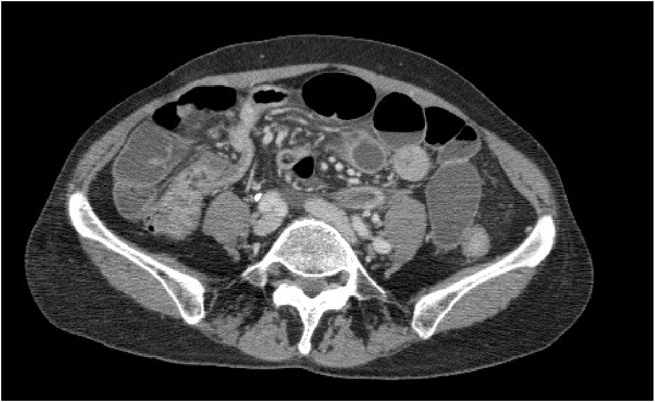

Abdominal computed tomography (CT): The small intestine was generally dilated, and there was a closed loop-like appearance near the end of the ileum and surrounding fatty tissue opacity. A strangulated bowel obstruction was suspected (Fig. 1).

Fig. 1.

Closed-loop-like findings are pointed out.